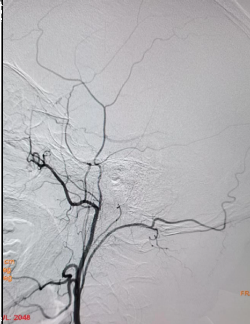

术前右侧椎动脉造影

病历夹什么径技·第152期|串联营病历夹:川陕大营_https://www.jmylbn.com_新闻资讯_第11张

病历夹什么径技·第152期|串联营病历夹:川陕大营_https://www.jmylbn.com_新闻资讯_第12张

病历夹什么径技·第152期|串联营病历夹:川陕大营_https://www.jmylbn.com_新闻资讯_第13张<<滑动查看下一张图片>>

术前左侧椎动脉造影

病历夹什么径技·第152期|串联营病历夹:川陕大营_https://www.jmylbn.com_新闻资讯_第14张

病历夹什么径技·第152期|串联营病历夹:川陕大营_https://www.jmylbn.com_新闻资讯_第15张

病历夹什么径技·第152期|串联营病历夹:川陕大营_https://www.jmylbn.com_新闻资讯_第16张

<<滑动查看下一张图片>>

左侧颈总动脉造影

病历夹什么径技·第152期|串联营病历夹:川陕大营_https://www.jmylbn.com_新闻资讯_第17张

右侧颈总动脉造影

病历夹什么径技·第152期|串联营病历夹:川陕大营_https://www.jmylbn.com_新闻资讯_第18张

病历夹什么径技·第152期|串联营病历夹:川陕大营_https://www.jmylbn.com_新闻资讯_第19张

病历夹什么径技·第152期|串联营病历夹:川陕大营_https://www.jmylbn.com_新闻资讯_第20张